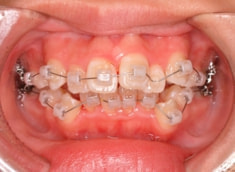

治療法:表の矯正(T21ブラケット)

治療前

治療後(1年2ヶ月後)